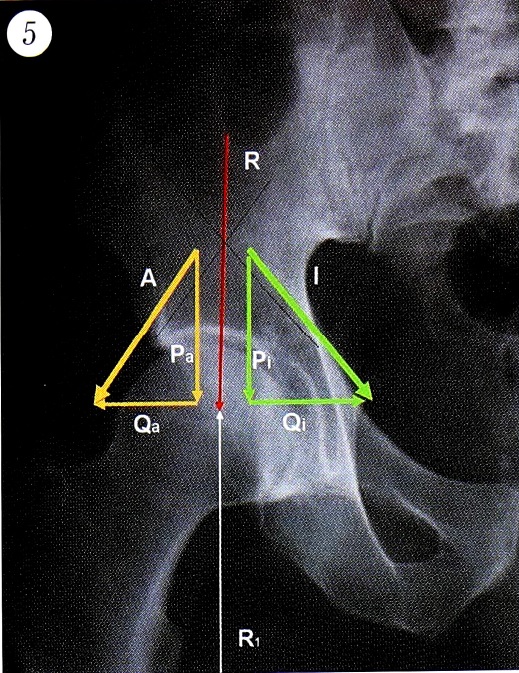

Если не учитывать действие отрицательного давления в суставе, то можно представить, что в случаях, когда вектор результирующей силы проходит вертикально, векторы сил ягодичных мышц и подвздошной мышцы имеют равный наклон. Это свидетельствует о равных значениях горизонтальной и вертикальной составляющих данных векторов при противоположных направлениях их горизонтальных составляющих (рис. 5).

Рис. 5. Распределение векторов сил при горизонтальном расположении сурсила. А — вектор силы отводящих мышц бедра; I — вектор силы подвздошной мышцы; Ра и Рi — вертикальные составляющие, (Qа и Qi — горизонтальные составляющие, R — результирующая сила, R1 — сила реакции опоры.